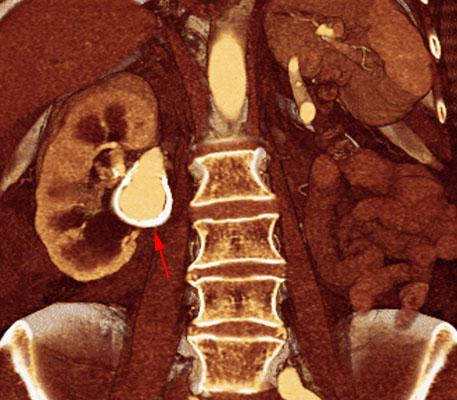

Los estudios de imagen juegan un papel impotante em el diagnóstico de la hipertensión arterial secundaria siendo una de las causas los aneurisma de arterias renales.

Habitualmente los aneurismas a este nivel son hallazgos incidentales y su estudio puede hacerse mediante Ecografía, Angio RM y AngioTC siendo este último un excelente método de despistaje de esta patología tanto por su disponibilidad actual como por las excelentes imágenes volumétricas que proporciona facilitando su localización y comprensión.

La angiografia por sustracción digital debe reservarse para embolización endovascular.